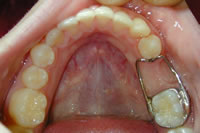

When a primary tooth is lost prematurely the teeth can drift into the new space crowding out the permanent tooth that is supposed to erupt into that space in the future. A space maintainer keeps baby teeth from shifting into the space where the tooth was lost so the permanent tooth can erupt in its natural proper space. As the permanent tooth erupts, Dr. Debian or one of his Associates will remove the appliance. Space maintainers can help eliminate the need for extensive orthodontics in the future.

band loop space maintainer

erupting tooth